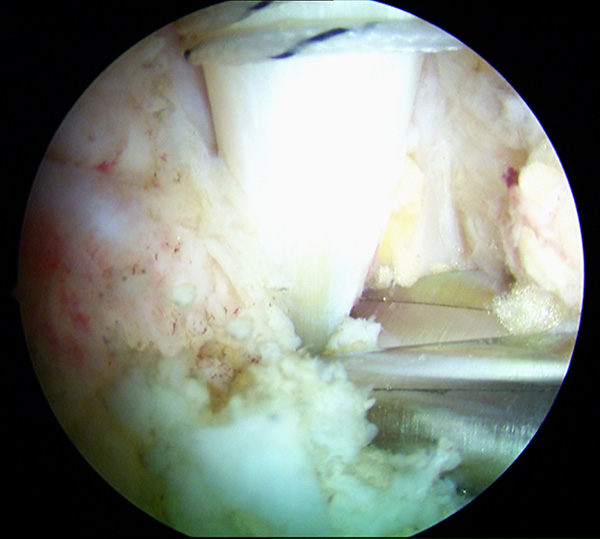

Abbildung 4, Video 1

Einführen des 4,0 mm Arthroskops über den posterolateralen Zugang und des Shavers über das posteromediale Portal. Es wird zunächst ein Weichteildebridement im Kagerschen Raum durchgeführt, bis die Flexor hallucis longus-Sehne (FHL) identifiziert werden kann (siehe auch Kapitel „Dorsale Arthroskopie des oberen und unteren Sprunggelenks“, Abbildungen 5-10).

Zum Lesen der Bildbeschreibung und zur Vollansicht bitte das Bild anklicken. Foto: M. Galla.